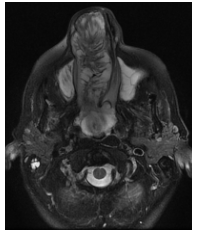

En RM, secuencia en T1, la lesión se observa hipo-isointensa y se proyecta desde orificio nasal hasta Cavum y coana, con aspecto de lesión solida expansiva ubicada sobre seno maxilar derecho que se extiende alrededor de la pared interna del seno nasal hacia la fosa nasal homolateral y se proyecta hasta senos frontales y presenta erosión de la lámina papirácea (Figura 5 – 6 – 7).